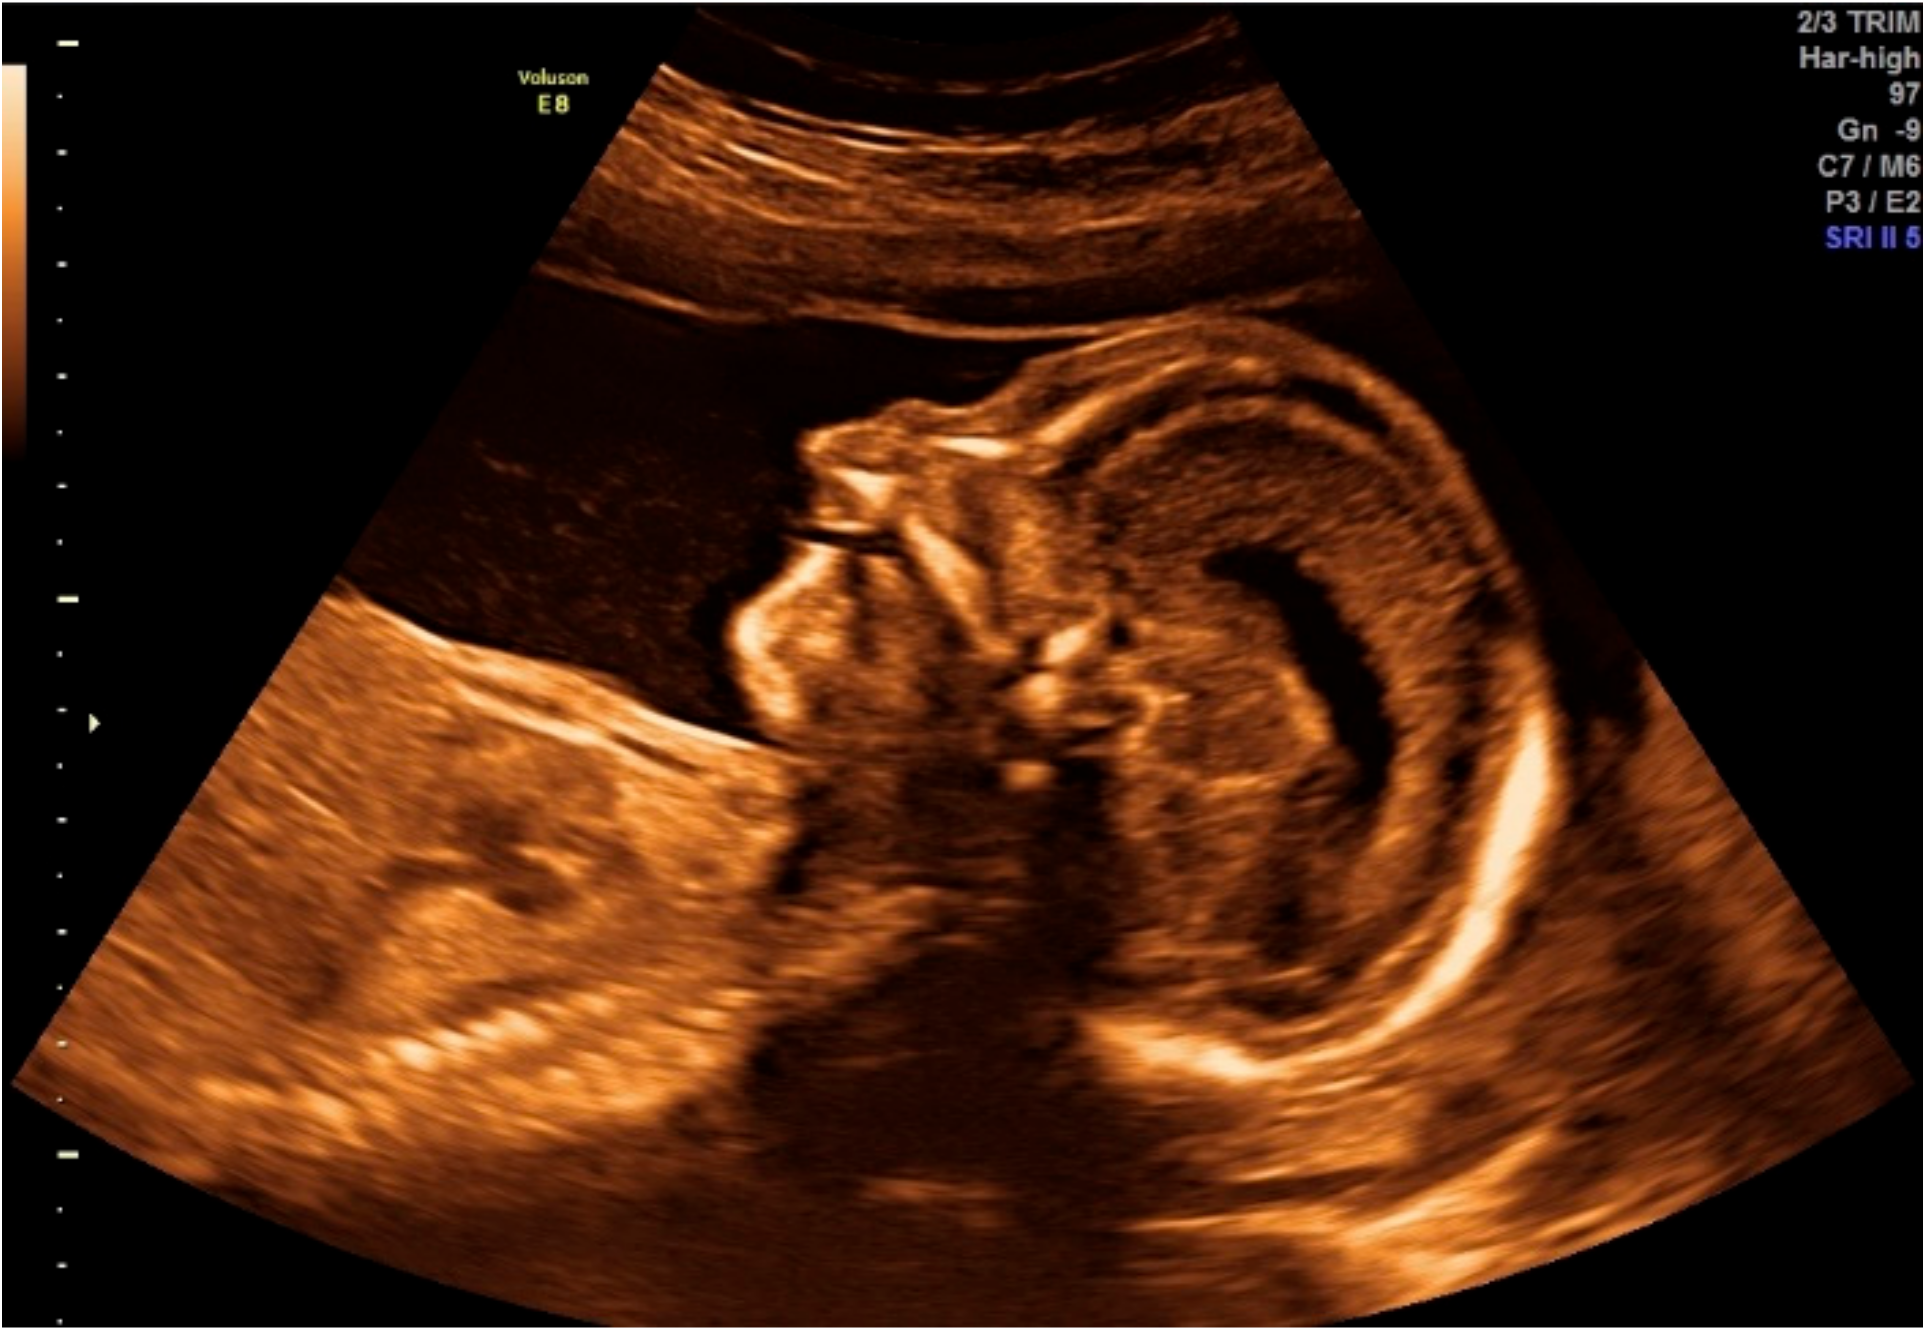

2.1.1. Obstetric Information